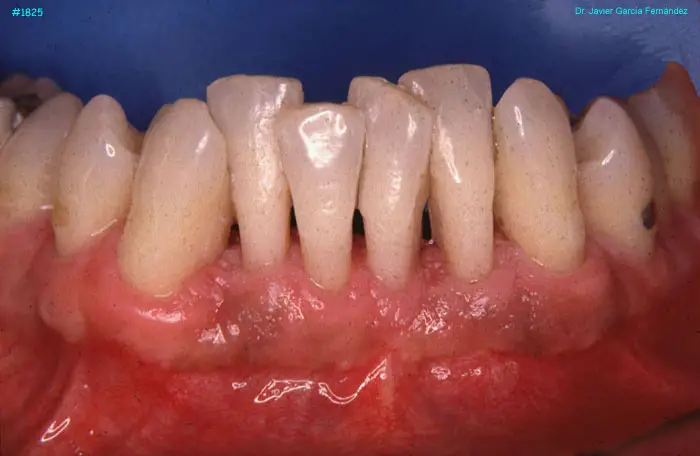

image 91